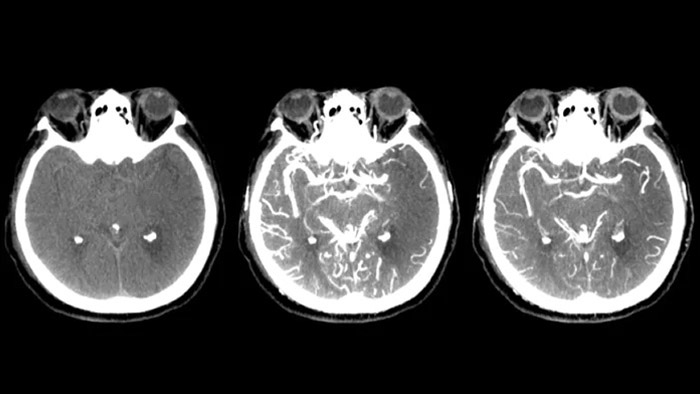

Drei SmartCT Aufnahmen

CT-artige Darstellung

SmartCT Soft Tissue generiert eine CT-artige Darstellung des Weichgewebes und erleichtert die Schlaganfalldiagnose auf drei Arten: Ein kontrastmittelfreier Scan hilft bei der Erkennung früher ischämischer Veränderungen. Ein Scan der frühen Phase hilft bei der Identifizierung des proximalen Verschlusses. Ein kontrastmittelverstärkter Scan der Spätphase unterstützt die Erkennung von Kollateralen.